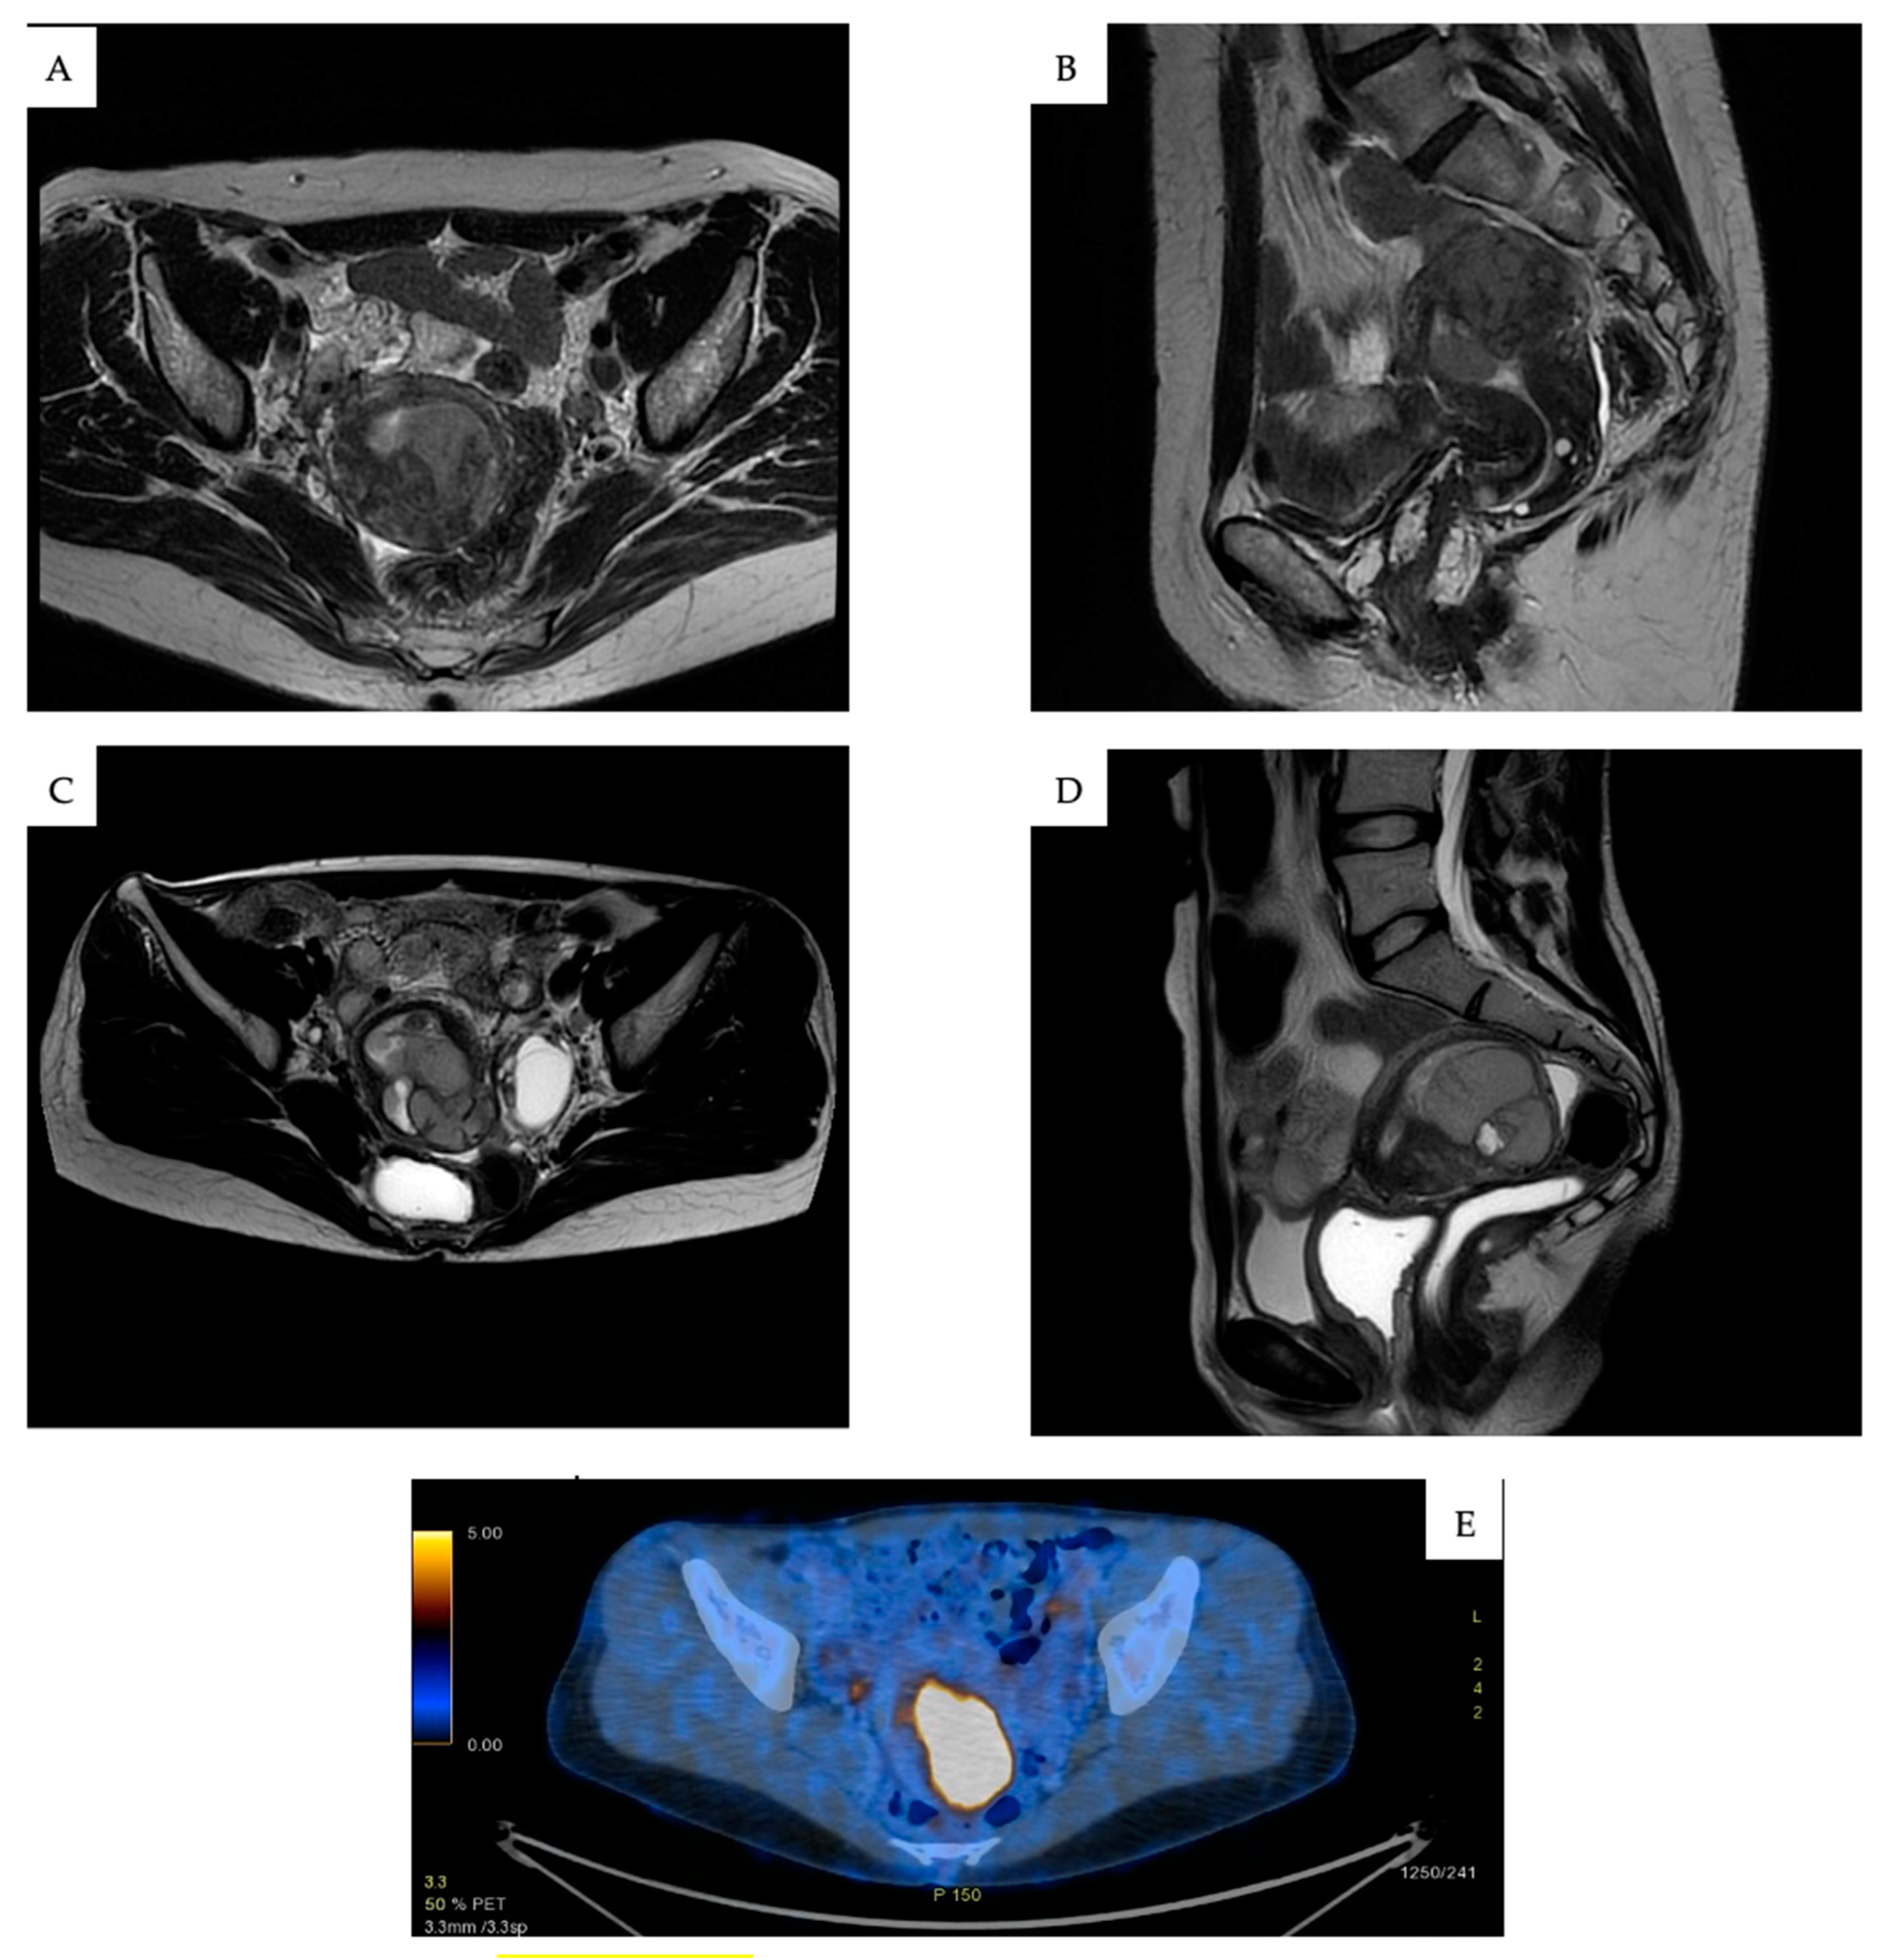

- Koyama, T.; Togashi, K.; Konishi, I.; Kobayashi, H.; Ueda, H.; Kataoka, M.L.; Kobayashi, H.; Itoh, T.; Higuchi, T.; Fujii, S.; et al. MR Imaging of Endometrial Stromal Sarcoma: Correlation with Pathologic Findings. Am. J. Roentgenol. 1999, 173, 767–772. [Google Scholar] [CrossRef]

- Ueda, M.; Otsuka, M.; Hatakenaka, M.; Sakai, S.; Ono, M.; Yoshimitsu, K.; Honda, H.; Torii, Y. MR Imaging Findings of Uterine Endometrial Stromal Sarcoma: Differentiation from Endometrial Carcinoma. Eur. Radiol. 2001, 11, 28–33. [Google Scholar] [CrossRef]

- Huang, Y.-L.; Ueng, S.-H.; Chen, K.; Huang, Y.-T.; Lu, H.-Y.; Ng, K.-K.; Chang, T.-C.; Lai, C.-H.; Lin, G. Utility of Diffusion-Weighted and Contrast-Enhanced Magnetic Resonance Imaging in Diagnosing and Differentiating between High- and Low-Grade Uterine Endometrial Stromal Sarcoma. Cancer Imaging 2019, 19, 63. [Google Scholar] [CrossRef]

- Fujiishi, K.; Nagata, S.; Kano, R.; Kubo, C.; Shirayanagi, M.; Ozaki, M.; Yamamoto, T.; Nakanishi, K.; Kamiura, S.; Nakatsuka, S. JAZF1–SUZ12 Endometrial Stromal Sarcoma Forming Subserosal Masses with Extraordinary Uptake of Fluorodeoxyglucose on Positron Emission Tomography: A Case Report. Diagn. Pathol. 2019, 14, 110. [Google Scholar] [CrossRef]